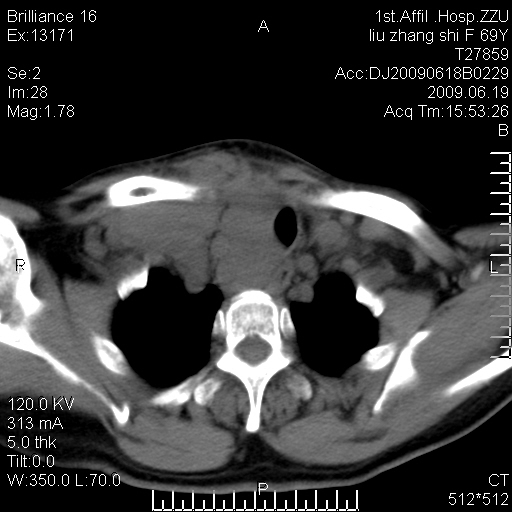

标题: CT26782:女,69岁,颈部占位,3天后公布病理结果。

【病理证实系列】女,69岁,颈部占位,有病理结果,3天后公布。(由于病例时间较久,临床资料不全,请网友见谅)本系列将有几百种常见、少见及罕见病例,均经病理证实。病例资料来自郑州大学第一附属医院。与网友共享,本人有空就发。

支持甲状腺癌广泛侵及周围结构并颈部淋巴结转移。

鉴别:淋巴瘤、恶性神经源性病变、恶性纤维组织细胞瘤。

病理结果:颈部非霍奇金淋巴瘤。

右侧甲状腺确实有问题